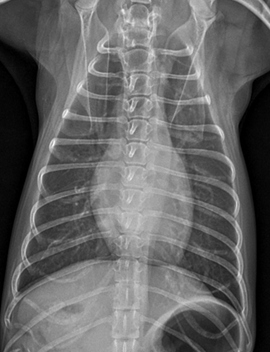

일주일 후 내원한 아이는 식욕도 많이 좋아지고 호흡도 좋아졌습니다. 방사선과 초음파입니다.

방사선상 유의미하게 심장 크기가 줄어들고 폐부종은 모두 사라졌습니다!